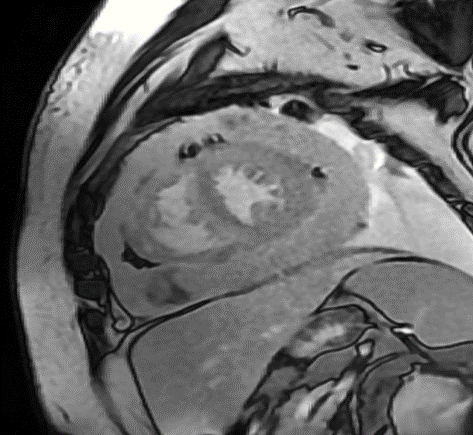

A 33-year-old man with no medical history or environment exposures, presented with dyspnea, nausea, and vomiting. He was tachycardic, with jugular venous distension, pulsus paradoxus, low voltage QRS and echocardiogram (TTE) showed a large pericardial effusion with ventricular interdependence. He underwent pericardiocentesis with negative fluid studies, including cytology. Two months later he represented with dyspnea and pleuritic chest pain, was diagnosed with pericarditis, and found to have recurrent pericardial effusion without tamponade. He was treated with aspirin and colchicine and discharged, with surveillance TTE showing a stable pericardial effusion but with significant adhesions and constrictive physiology (confirmed on right heart catheterization). Negative QuantiFERON was obtained and Anakinra started. Two months later he remained symptomatic with new pleural effusions and was sent for positron emission tomography scan which revealed diffuse intensely hypermetabolic pericardial thickening/fluid, up to 3.8 cm in maximal thickness and increased uptake in mediastinal nodes. Next, a cardiac MRI showed extensive circumferential thickening of the pericardial space approximately 2.5 cm in thickness. Both the visceral and parietal pericardium exhibited extensive scattered delayed hyperenhancement. Subsequent pericardial biopsy showed markedly fibrotic pericardium and pathology showed biphasic malignant pericardial mesothelioma. Immunosuppressive medications were stopped, and he underwent thoracentesis. After multidisciplinary discussions, he was started on nivolumab every two weeks and ipilimumab with a plan for surgery based on response to therapy. However, progressive symptoms and worsening constriction physiology led to palliative consultation and comfort care transition, with him dying shortly after.